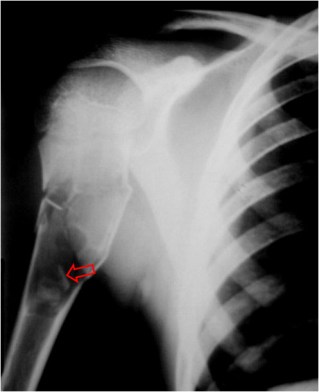

SIGNO DEL FRAGMENTO CAÍDO

Pequeño fragmento óseo que yace en la posición más declive de una lesión ósea radiolucente y que corresponde a una fractura patológica de un fragmento de cortical adelgazada en un quiste óseo solitario. El hecho de que el fragmento caiga solo es posible por el contenido líquido de la lesión, lo que descarta todas las lesiones óseas solitarias sólidas. Aunque este signo fue descrito en radiografía convencional, puede verse también en TC y en resonancia magnética.

Kileen KL. The fallen fragment sign. Radiology 1998; 207:261-262.